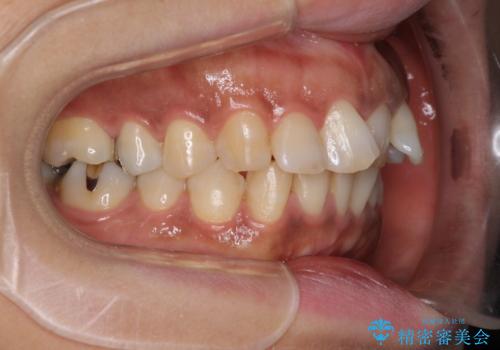

- 上下前歯のデコボコ改善をインビザラインにて行いたいとのことで来院された患者様です。

インビザラインをご希望のことで、IPR(歯と歯の間を削る)などによりスペースを獲得して、排列していくこととしました。

骨格的に上下顎が左右にずれていたため、正中位置は現状を維持したまま歯列不正を解消していくことになります。